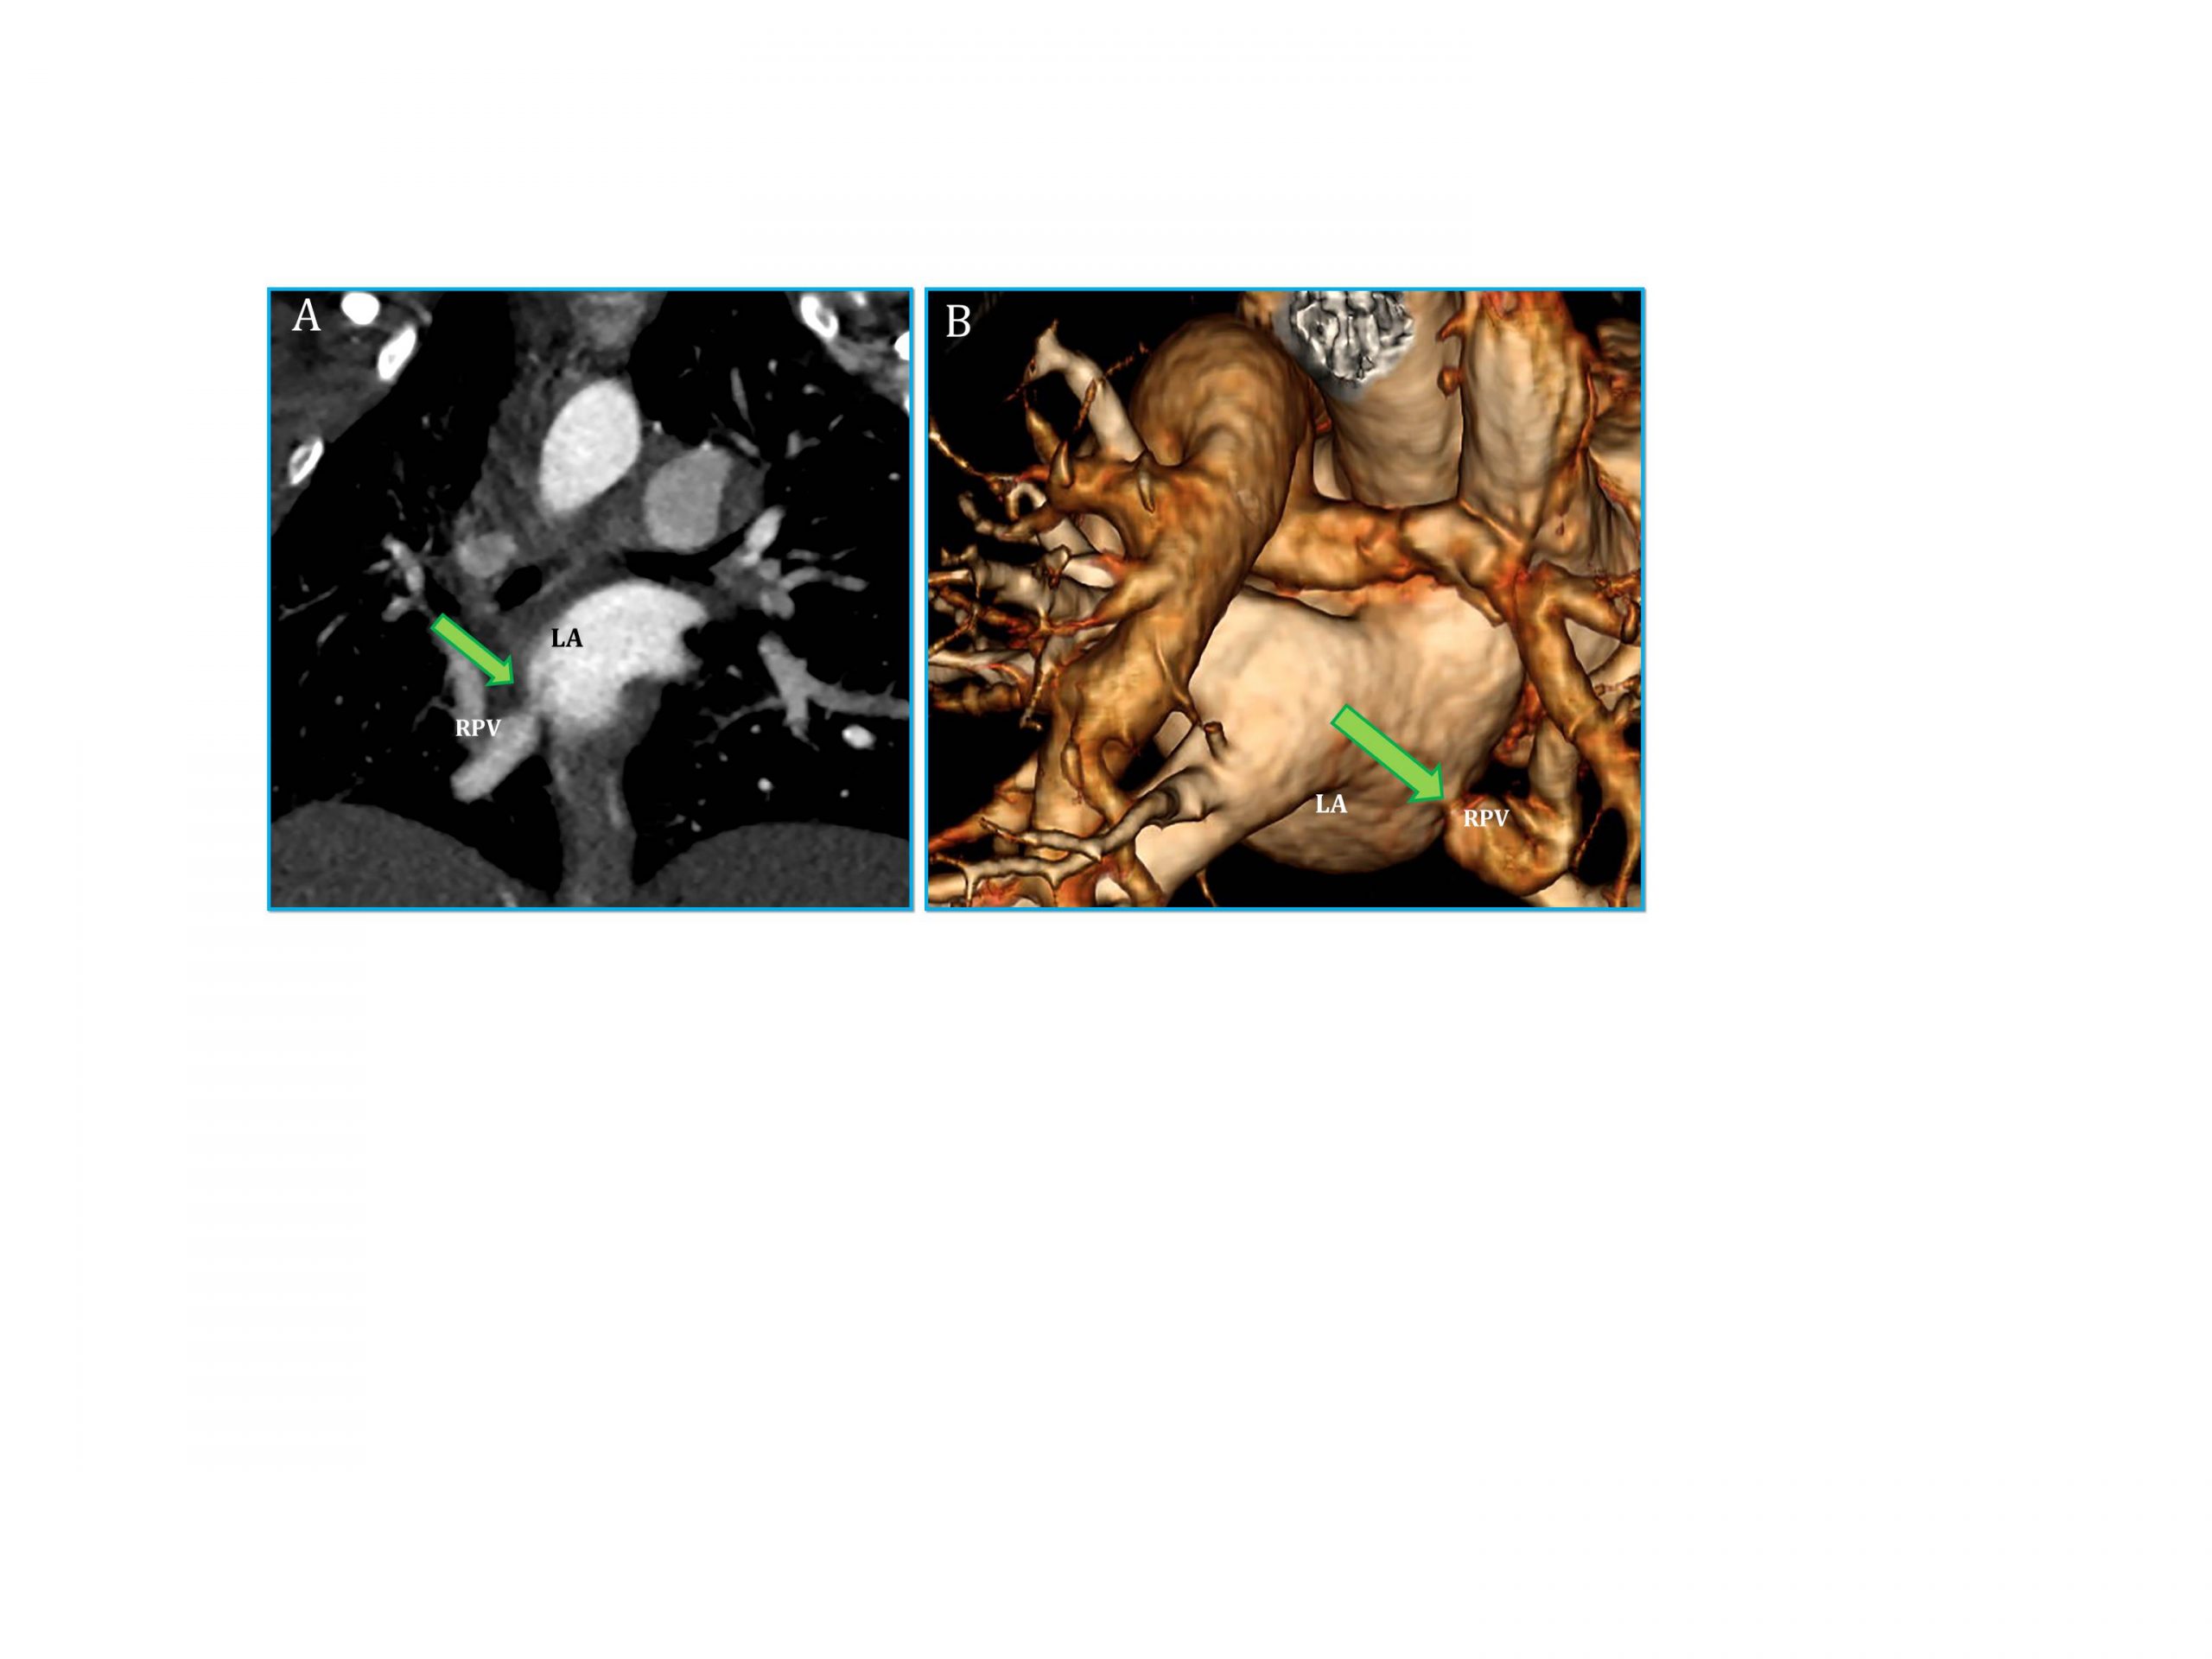

– CT scan showed stenosis at anastomosis site, measuring 1.3 x 1mm (Figure 2)